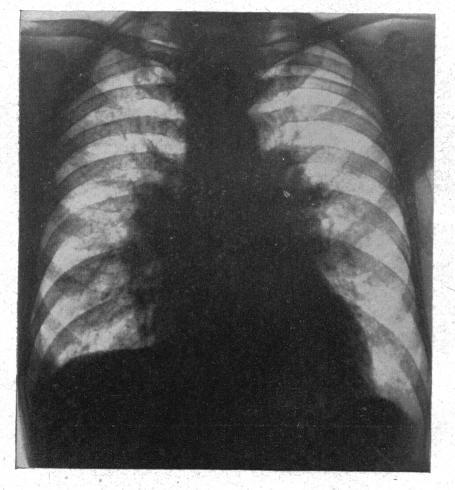

The radiology of acute pulmonary oedema.

Br Heart J. 1951 Oct;13(4):503-18. doi: 10.1136/hrt.13.4.503.